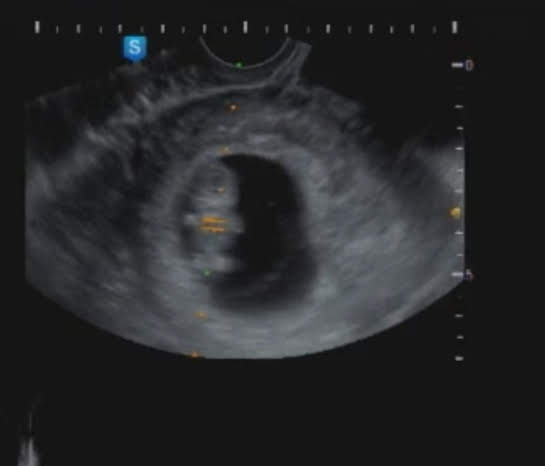

초음파를 배에 대고 보는데 ...

오마!! 너무 귀여운 곰 젤리가 한 마리 있는거에요~

세상에... 형태가 얼마나 귀엽던지 ㅋㅋ 초음파보는데 시간가는줄 모르고 봤네요